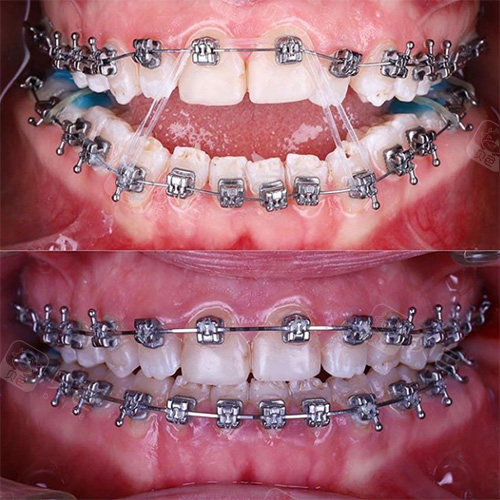

如果发现牙齿上下咬合不到一起,那么你一定要注意这不正常哦!无论是前牙还是后牙,都有可能出现这种情况,那么这种咬合不到一起的情况就是开颌。

多数的开颌情况多见于恒牙期,一般出现这样情况的人还伴随着有舔牙、咬唇、吮指、吐舌头等不良习惯,还有一种情况就是用嘴呼吸也会引起前牙开颌问题的出现。

一般来说,前牙开颌情况比较常见,而开颌也是正畸领域当中属于难度中上级别的类型,对于咬合、脸型、微笑线等多方面都要综合考量。如果是开颌高于5mm的,可能还会伴随骨骼问题,需要考虑是否需要进行手术。